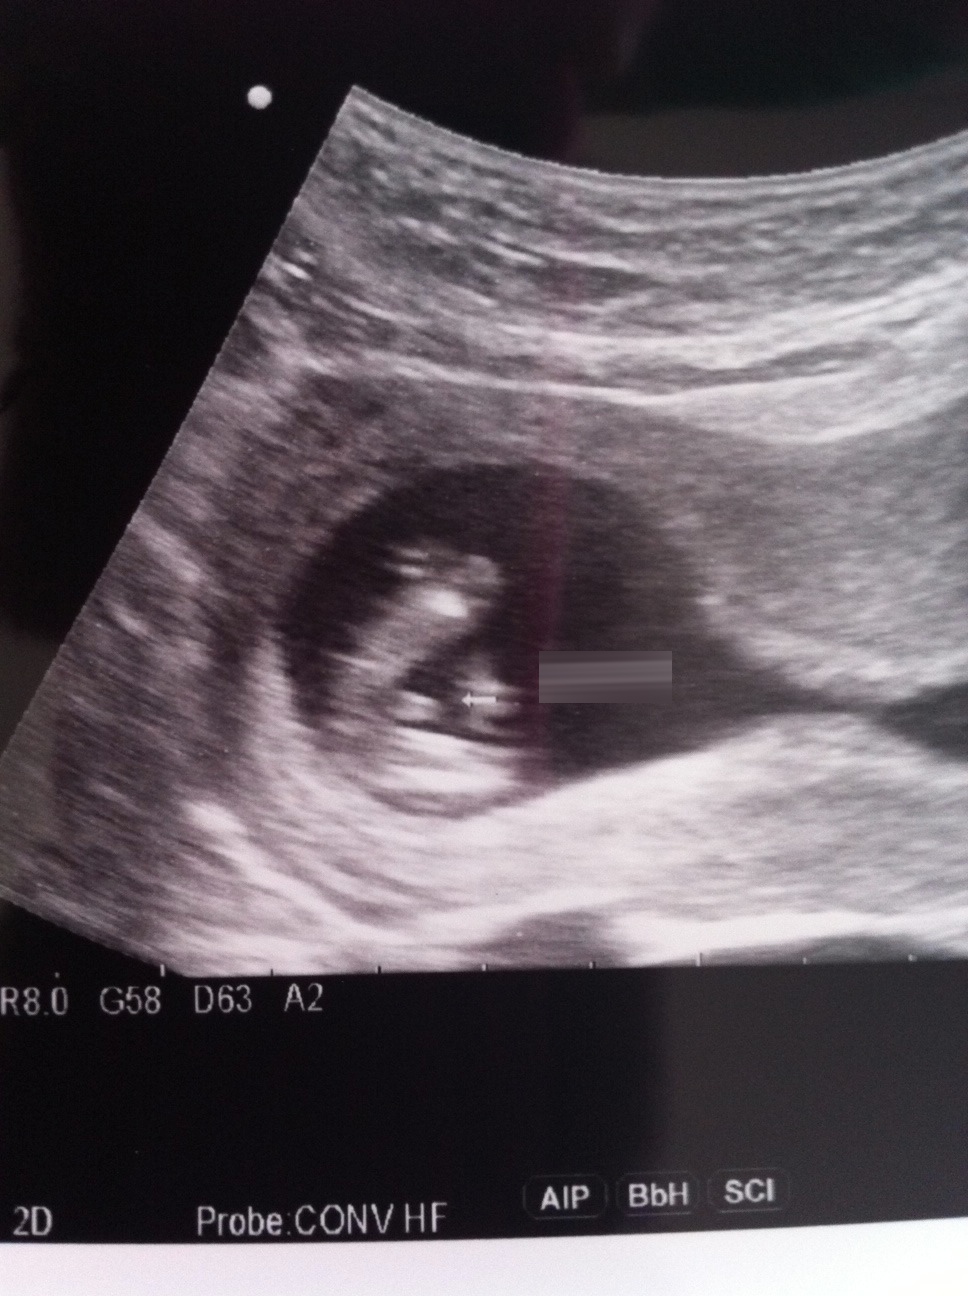

Looks pretty classic boy to me based on second pic. Sorry, I think you were hoping girl?

That's a boy, hun.

That last ultrasound looked to be very poor quality. This is really clear. I know it's not what you were hoping for but I think that is a definite boy. That is a penis and a textbook boy nub.

these new shots definitely look like a boy to me